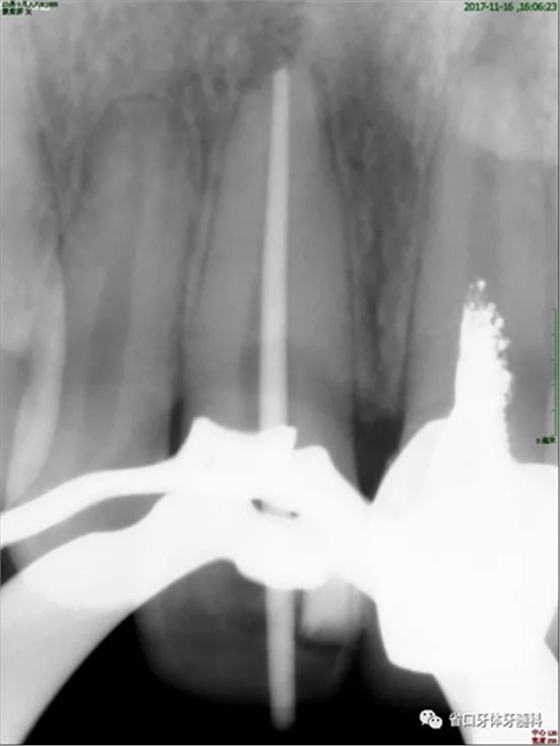

2周后復(fù)診:封藥存,患牙無不適,叩痛-,齦無紅腫。去封藥,清理根管,試主尖到位,沖洗、干燥,熱牙膠充填至釉牙骨質(zhì)界下2mm,照片顯示恰充。

圖4 試尖片